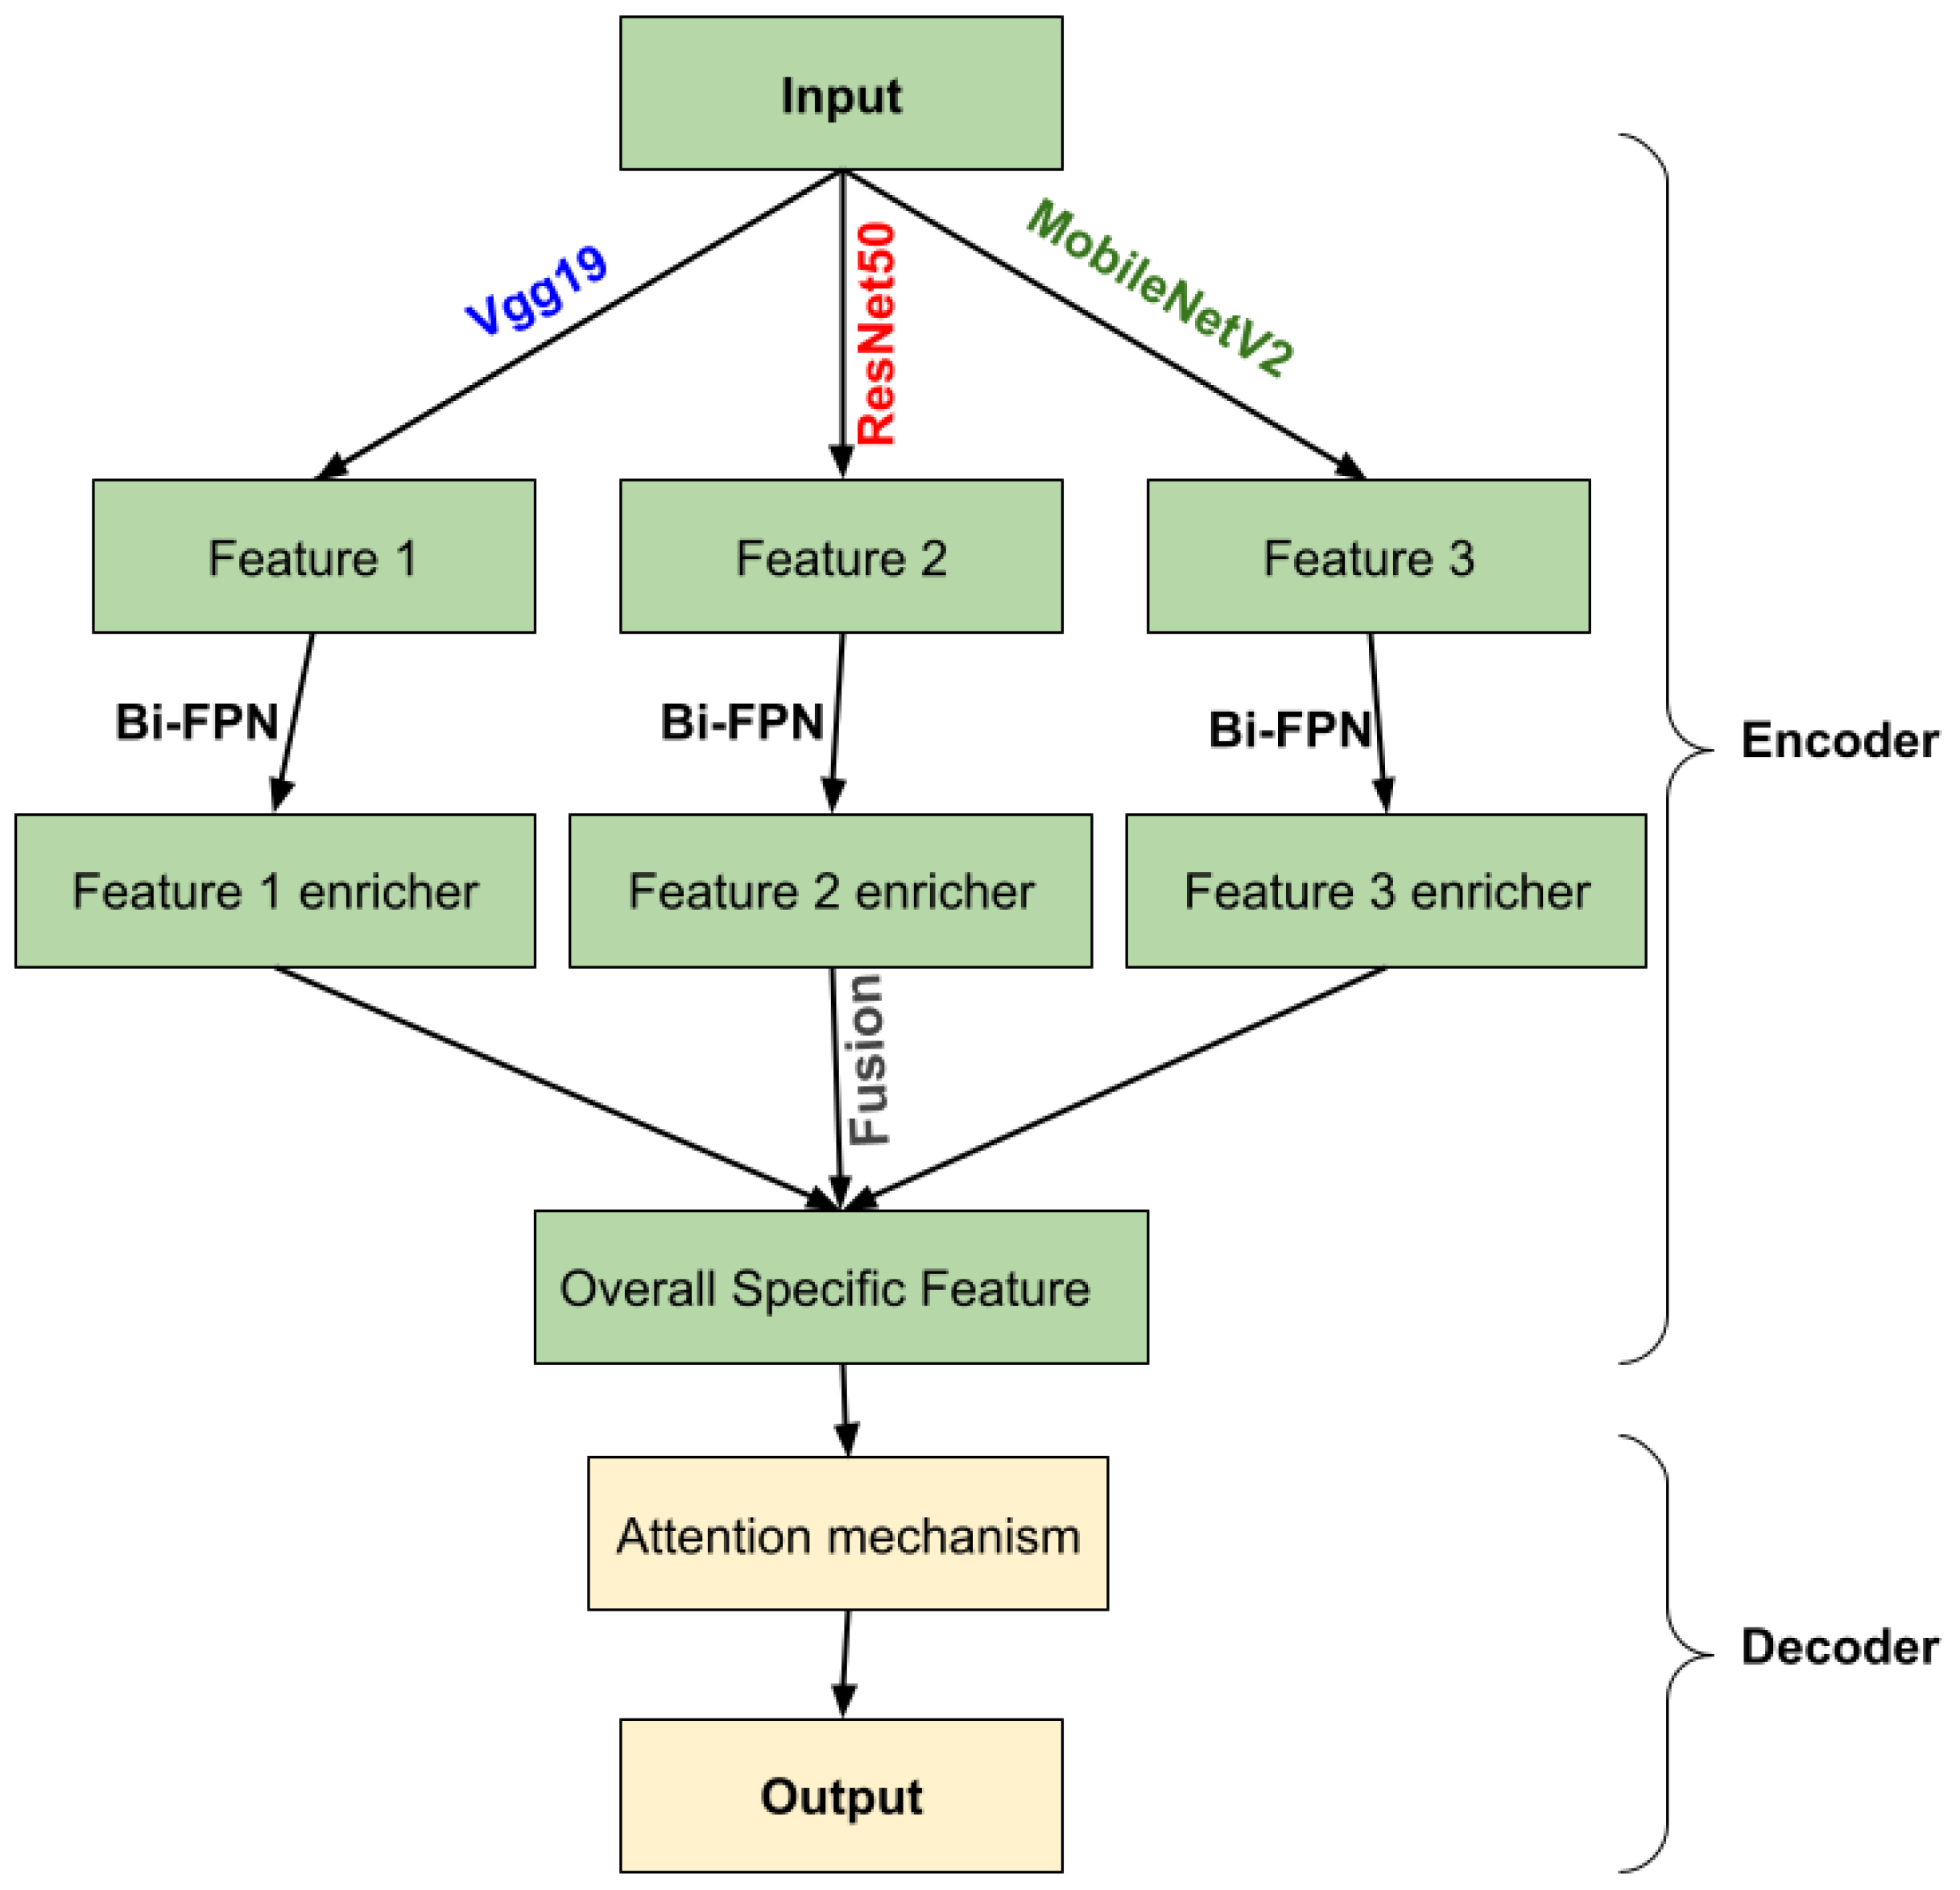

2.2. Methods

2.2.1. Encoder

Transfer Learning

- VGG-19

- ResNet50

- MobileNetV2

Bi-Directional Feature Pyramid Network (Bi-FPN)

2.2.2. Decoder